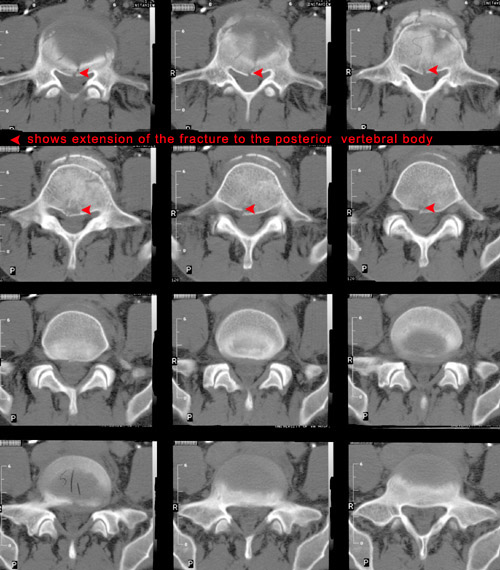

It is important that CT be performed to fully assess the spinal canal. The images below illustrate the appearance of a compression fracture as seen on CT.

Note that in the images below, the posterior vertebral body is not intact.

CT of lumbar compression fracture